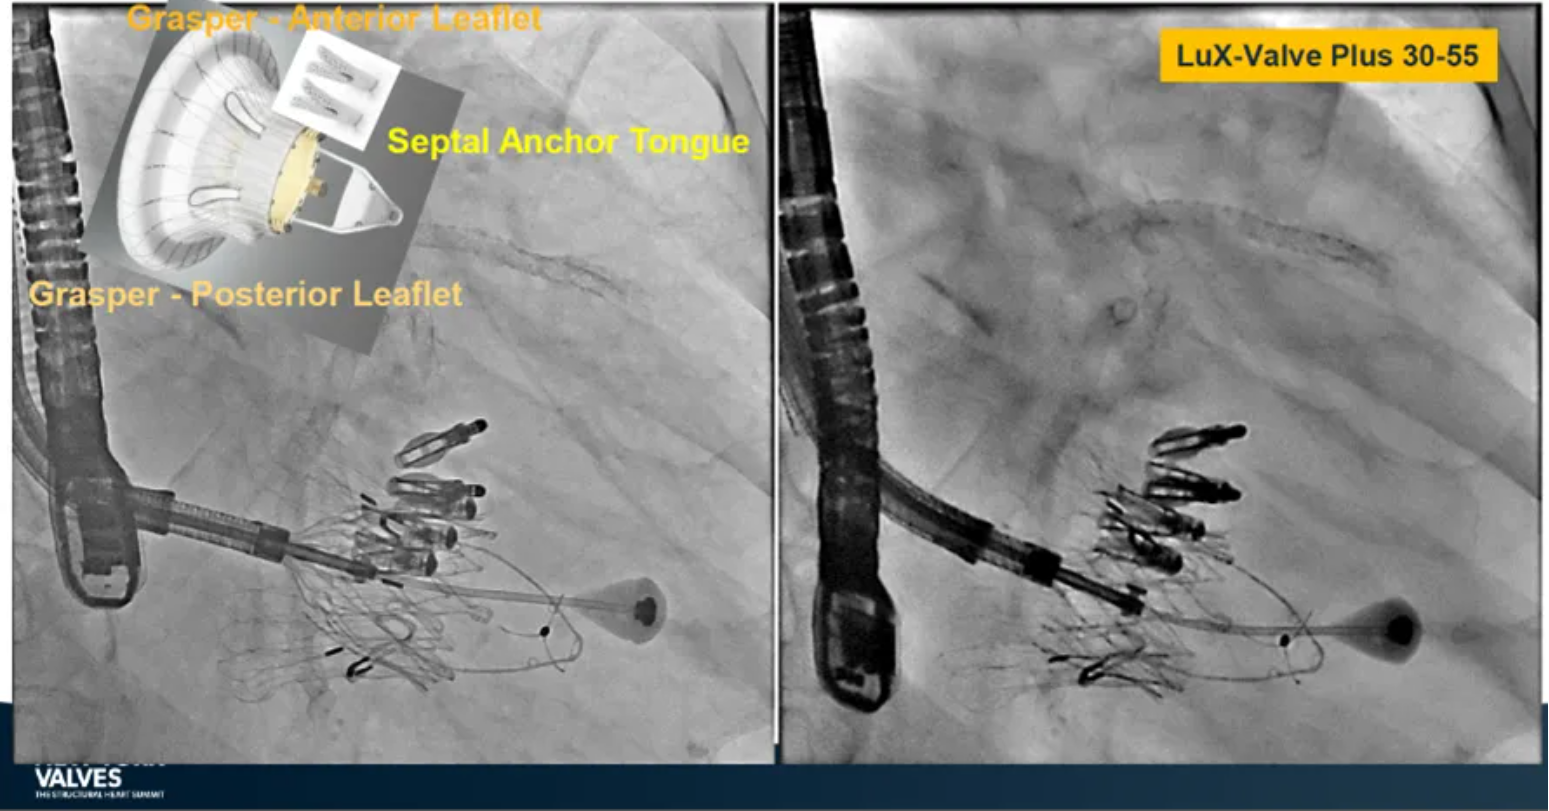

LuX-Valve Plus是健世科技(Jenscare,9877.HK)推出的全新一代經(jīng)頸靜脈三尖瓣置換系統(tǒng)(Transjugular Tricuspid Valve Replacement System),其創(chuàng)新性地采用頸靜脈作為手術(shù)入路,在不依賴徑向支撐力的情況下借助室間隔錨定、瓣葉夾持技術(shù)構(gòu)成其多重錨定結(jié)構(gòu),并通過(guò)自適應(yīng)編織環(huán)有效進(jìn)行心房側(cè)封堵,呈現(xiàn)更好的安全性和有效性。

來(lái)自中國(guó)香港瑪麗醫(yī)院(Queen Mary Hospital, Hong Kong, China)的Simon Lam教授在2024年紐約瓣膜會(huì)上分享了一例復(fù)雜案例,一名高齡男性患者在2年前行二尖瓣和三尖瓣TEER術(shù)式后繼發(fā)三尖瓣反流,遂再次行二尖瓣TEER術(shù)式和用LuX-Valve Plus行三尖瓣TTVR術(shù)式。

本次術(shù)式中,LuX-Valve Plus的植入緊隨二尖瓣修復(fù)術(shù)式之后,且并未取出前期植入的三尖瓣修復(fù)夾,這意味著LuX-Valve Plus在患者有過(guò)二尖瓣和三尖瓣修復(fù)夾植入情況下的兼容性,并且?guī)?lái)了有效的治療結(jié)果。此外,這不僅體現(xiàn)了LuX-Valve Plus可以與二尖瓣術(shù)式并行,更可以兼容三尖瓣原位的其他修復(fù)夾產(chǎn)品。